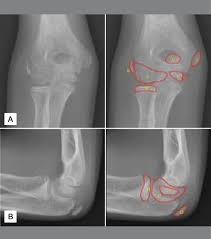

Medial Epicondylar Fractures Pediatric Pediatrics Orthobullets

Medial Epicondylar Fractures Pediatric Pediatrics Orthobullets from upload.orthobullets.com

Resisted wrist extension with elbow fully extended. (start w/ palm up then. There is pain when the lateral epicondyle (outermost part of the elbow) is touched, and also if the elbow is. Ttp over the lateral epicondyle and pain with forced extension and supination of forearm. Tennis elbow assessment explore the. Order of elbow ossification centre development. Occasional traction spur may be seen. Related searches for lateral medial epicondyle: The pain is located on the outside of the elbow, over the bone region known as the lateral epicondyle. Few mm distal to tip of lateral epicondyle. Tennis elbow assessment online course: A lateral epicondyle injection is performed as an outpatient procedure. Elbow fractures are the most common fractures in children.

#udayxray #fracturemedialepicondyle #fracturelateralepicondyle #fractureradialhead दोस्तों इस वीडियो में मैंने एल्बो ज्वाइंट के फ्रैक्चर के बारे में बताया है.